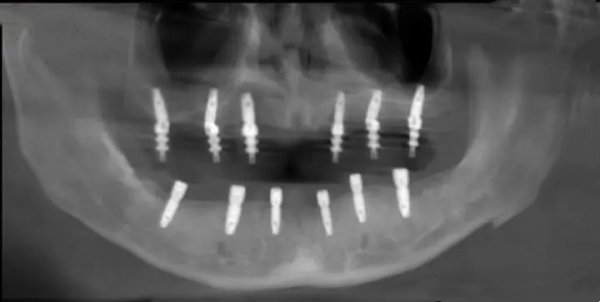

1. 于都瑞德口腔:技术强,成功概率95%+

为什么推荐:医生团队都是正骨科出身,有10年以上种植经验。种植牙成功概率高达95%+,比其他医院高10%!

真实实例:我朋友上周在瑞德口腔做了种植牙,医生用即刻负重技术,种完当天就能吃东西!

江西于都哪个店种植牙好优势:技术强、价格透明、无隐形消费

价格参考:种植牙3990元起(韩国奥齿泰)